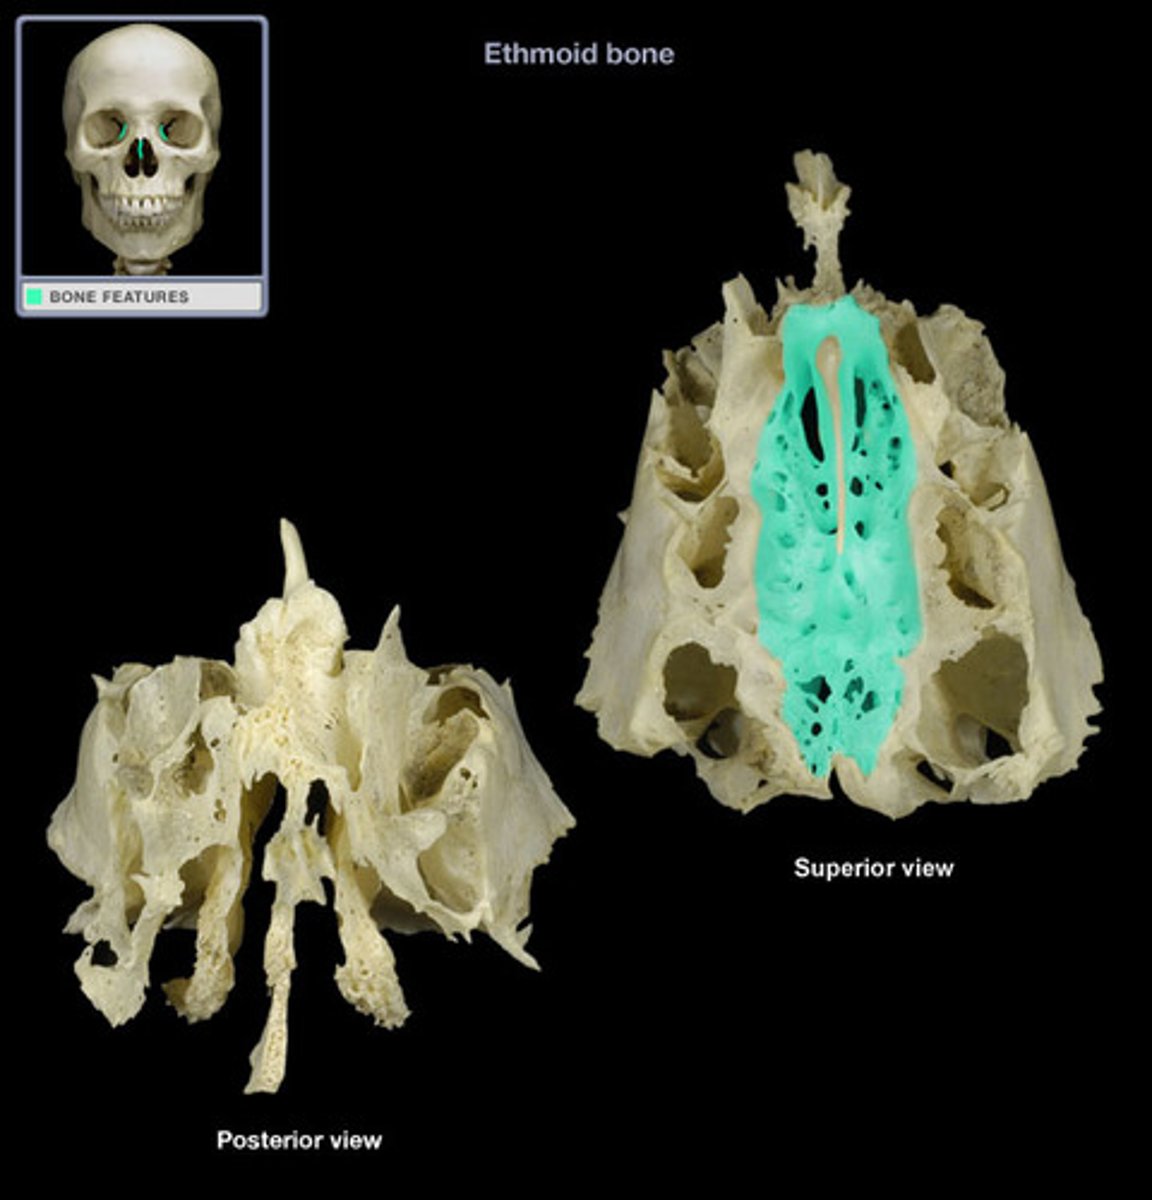

ethmoid bone

cribriform plate

crista galli

perpendicular plate

ethmoidal labyrinth

superior nasal concha

middle nasal concha